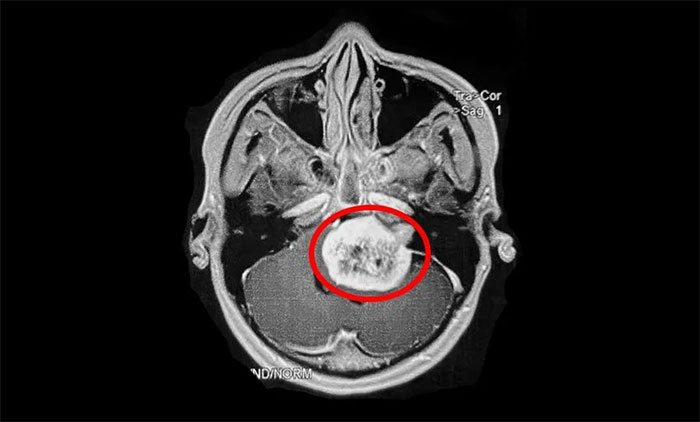

值得注意的是,听神经瘤早期表现易与耳聋及其他一些颅脑肿瘤混淆,出现相应症状时,患者应及早到具备专科诊疗能力的医疗机构,通过听力学检查、面神经功能检查、前庭功能检查、影像学检查(听神经瘤主要检查手段),即可明确诊断。

▲ 影像学检查是听神经瘤主要检查手段(示意图)

听神经瘤的治疗并非易事。对于已生长较大及已出现症状的肿瘤,治疗策略包括手术治疗和立体定向放射治疗,选择取决于肿瘤分期、位置、生长速度、是否囊性变、患侧及对侧听力水平、患者年龄、身体状况等。其中,手术是听神经瘤主要治疗方式。